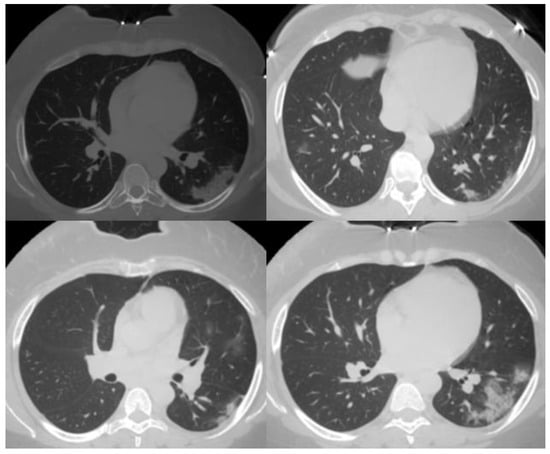

| 1 | Very low | Normal or non-infectious CT findings. |

| 2 | Low | CT findings incompatible with COVID-19: bronchitis, infectious bronchiolitis, and bronchopneumonia. |

| 3 | Equivocal/uncertain | CT findings of other viral pneumonia or non-infectious results: perihilar GGO, homogenous extensive GGO, and GGO with smooth interlobular septal thickening. |

| 4 | High | CT findings are similar to those for CO-RADS 5, but a lack of contact with the visceral pleura, located unilaterally, in a peri-broncho vascular distribution, or when the findings are superimposed on pre-existing lung abnormalities. |

| 5 | Very high | Typical CT findings: ground-glass opacities with or without consolidations in lung regions close to visceral pleural surfaces and multifocal bilateral distribution. |